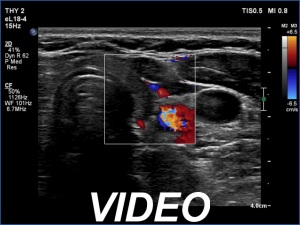

Ultrasonography: The thyroid was echonormal. There were multiple hypoechogenic areas with ill-defined borders in both lobes. According to the hypoechogenic areas, the vascularization was practically absent.

Ultrasonography: The thyroid became hypoechogenic and decreased significantly in size while the vascularization was significantly increased.

Ultrasonography: The thyroid became hypoechogenic and decreased further in size. The vascularization was average.

Ultrasonography: Compared with the last examination, the thyroid was less hypoechoic. The vascularization was decreased.